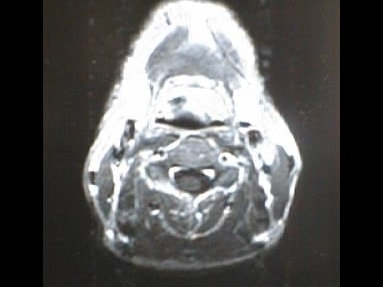

中咽頭末期がんMRI画像②

入院当時MRI画像②

中咽頭末期がん消滅時MRI画像②

入院3か月後癌消滅MRI画像②